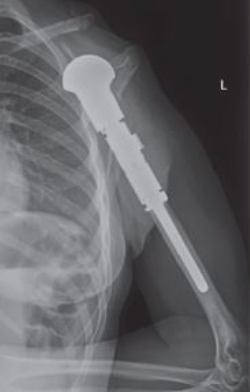

This is an x-ray image of an endoprosthesis in the arm. The prosthesis is made to match the length of the original bone and soft tissue reconstruction covers the prosthesis to maximize functioning postoperatively.